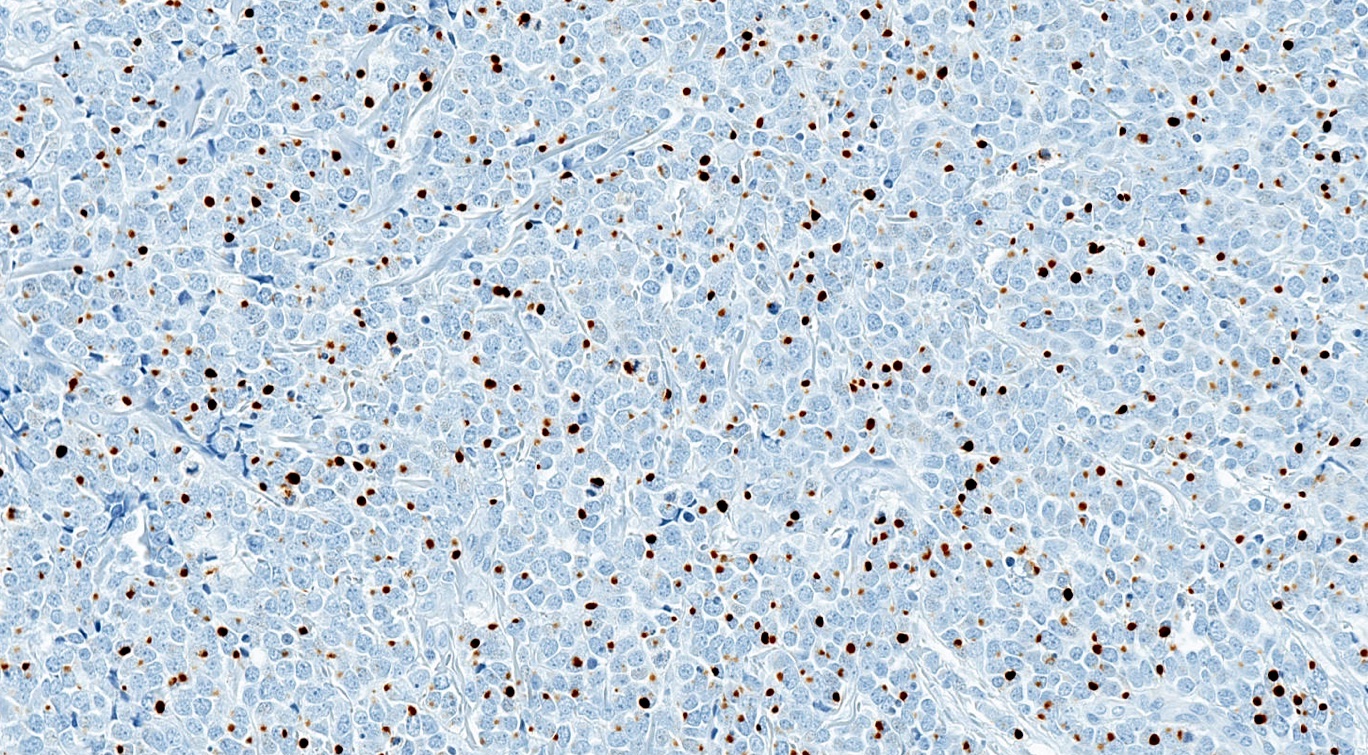

Microscopic (histologic) images

Positive stains

- Broad spectrum keratins: CAM 5.2, AE1 / AE3 (paranuclear, cytoplasmic or mixed pattern)

- CK20 (classic dot-like paranuclear pattern)

- Chromogranin, synaptophysin, CD56, neuron specific enolase

- Neurofilament (dot-like pattern)

- Variable MCPyV (nuclear pattern)